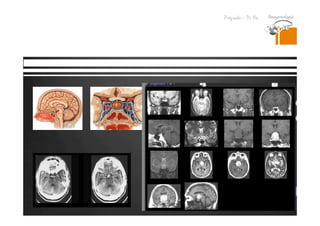

Lesiones isodensas en TC.

RESONANCIA MAGNETICA

DR. JULIO LAMA